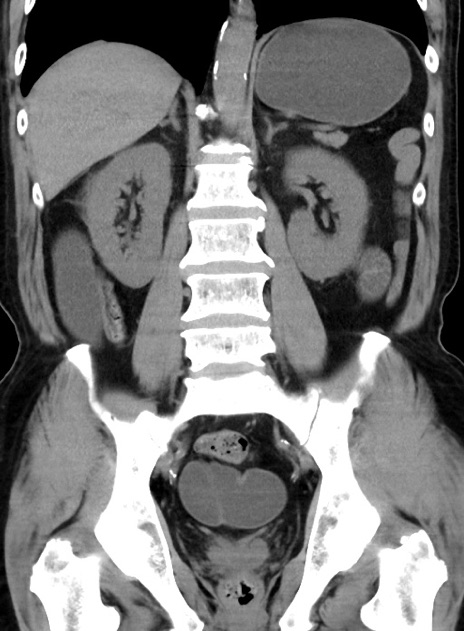

症例38(冠状断像)

【症例】70歳代 男性

【主訴】腹痛・嘔吐

【現病歴】昨晩より、嘔吐・腹痛あり。今朝になっても嘔吐あり。来院。

【既往歴】心臓バイパス手術、開腹胆摘、腸閉塞

【身体所見】BP 107/71mmHg、HR 116/min、腹部:平坦、軟、下腹部に軽度圧痛あり。反跳痛なし。

【データ】WBC 15100、CRP 0.32